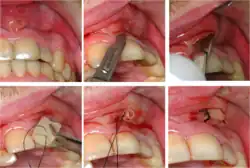

- Assessment of biting on individual teeth (which sometimes helps to localize the problem) or the separate cusps (may help to detect cracked cusp syndrome).

Plastic wedge to identify pain on biting from a fractured tooth -